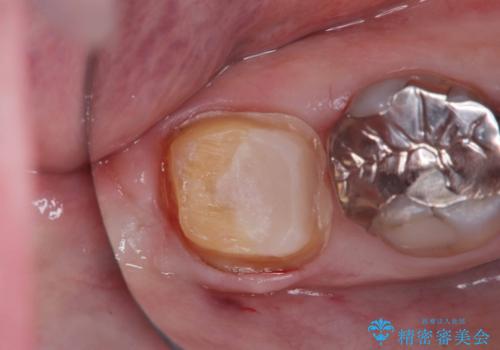

- 当院にメインテナンスで通っていただいている患者様です。銀歯の下の虫歯が大きくなってきたので、治療を行いました。

銀歯を外し虫歯を除去後、オールセラミッククラウンで治療を行いました。